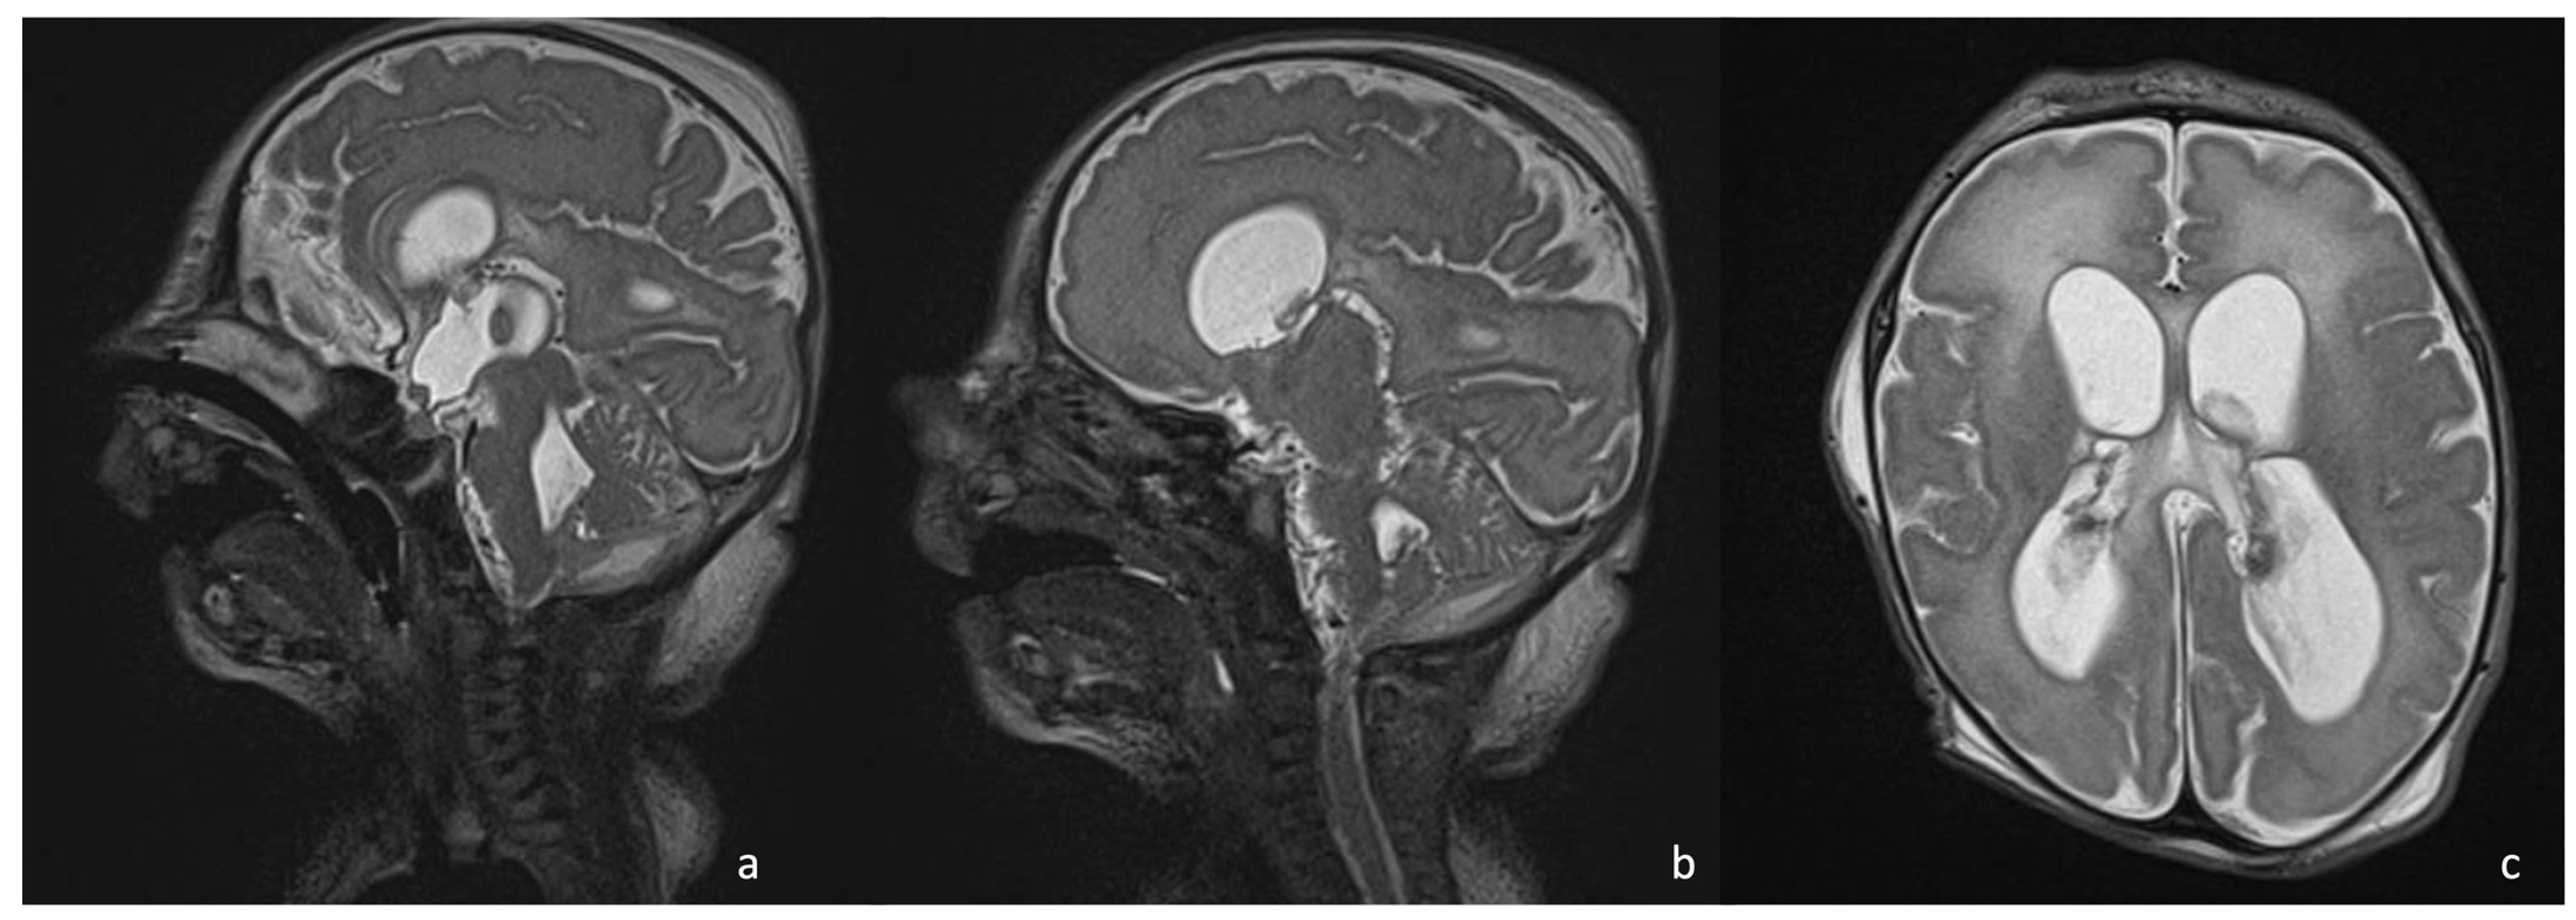

- Late cerebritis (5–14 days): Cerebritis progressively evolves to show a necrotic core and an initial encapsulation. This stage flows into and partly overlaps with the early capsule stage since this last represents a progression with similar, yet more advanced features of the late cerebritis stage. In MRI, the late cerebritis results in a focal formation characterized by a necrotic core, appearing inhomogeneous on both T1 and T2WI, without a complete and regular contrast peripheral enhancement, yet with a defined diffusion restriction on DWI/ADC. On the US, the appearance is similar to the early cerebritis, yet the lesion appears more focal and the core starts becoming hypoechogenic, similar to CT showing a significantly hypodense core in the lesion with irregular and incomplete peripheral enhancement. Early capsule formation (14–30 days): The cerebritis is becoming an abscess since the capsule is evident, yet it is incomplete and thin and appears as a hyperintense rim on T1WI and a hypointense rim on T2WI with contrast enhancement on T1WI.

- Early capsule formation (2 weeks to 2 months): the lesion presents diffusion restriction on DWI/ADC, mainly in relation to hypercellularity. Sonographically, the lesion presents a well-defined hypoechoic core and an incomplete hyperechoic rim. CT shows a well-defined hypodense core and an incomplete peripheral enhancement.

- Late capsule formation (weeks to months): The parenchymal abscess presents a necrotic core, appearing hypointense on T1WI and hyperintense on T2WI with diffusion restriction on DWI/ADC. The capsule is inhomogeneously thick, appearing thicker towards the cortex and thinner towards the ventricles, appears isointense on T1WI and hypointense on T2WI, and presents an intense enhancement. On the US, the abscess presents a well-defined hypoechoic core and a complete hyperechoic rim, pairing CT that shows a well-defined hypodense core and a complete peripheral enhancement.

7.3. Gram-Negative Bacteria and Abscesses